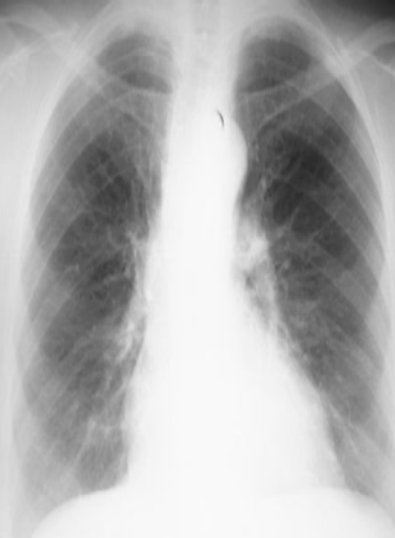

What view

PA (lower diapjragm, full lungs/large, horizontally oriented clavicales, scapula not displaced)